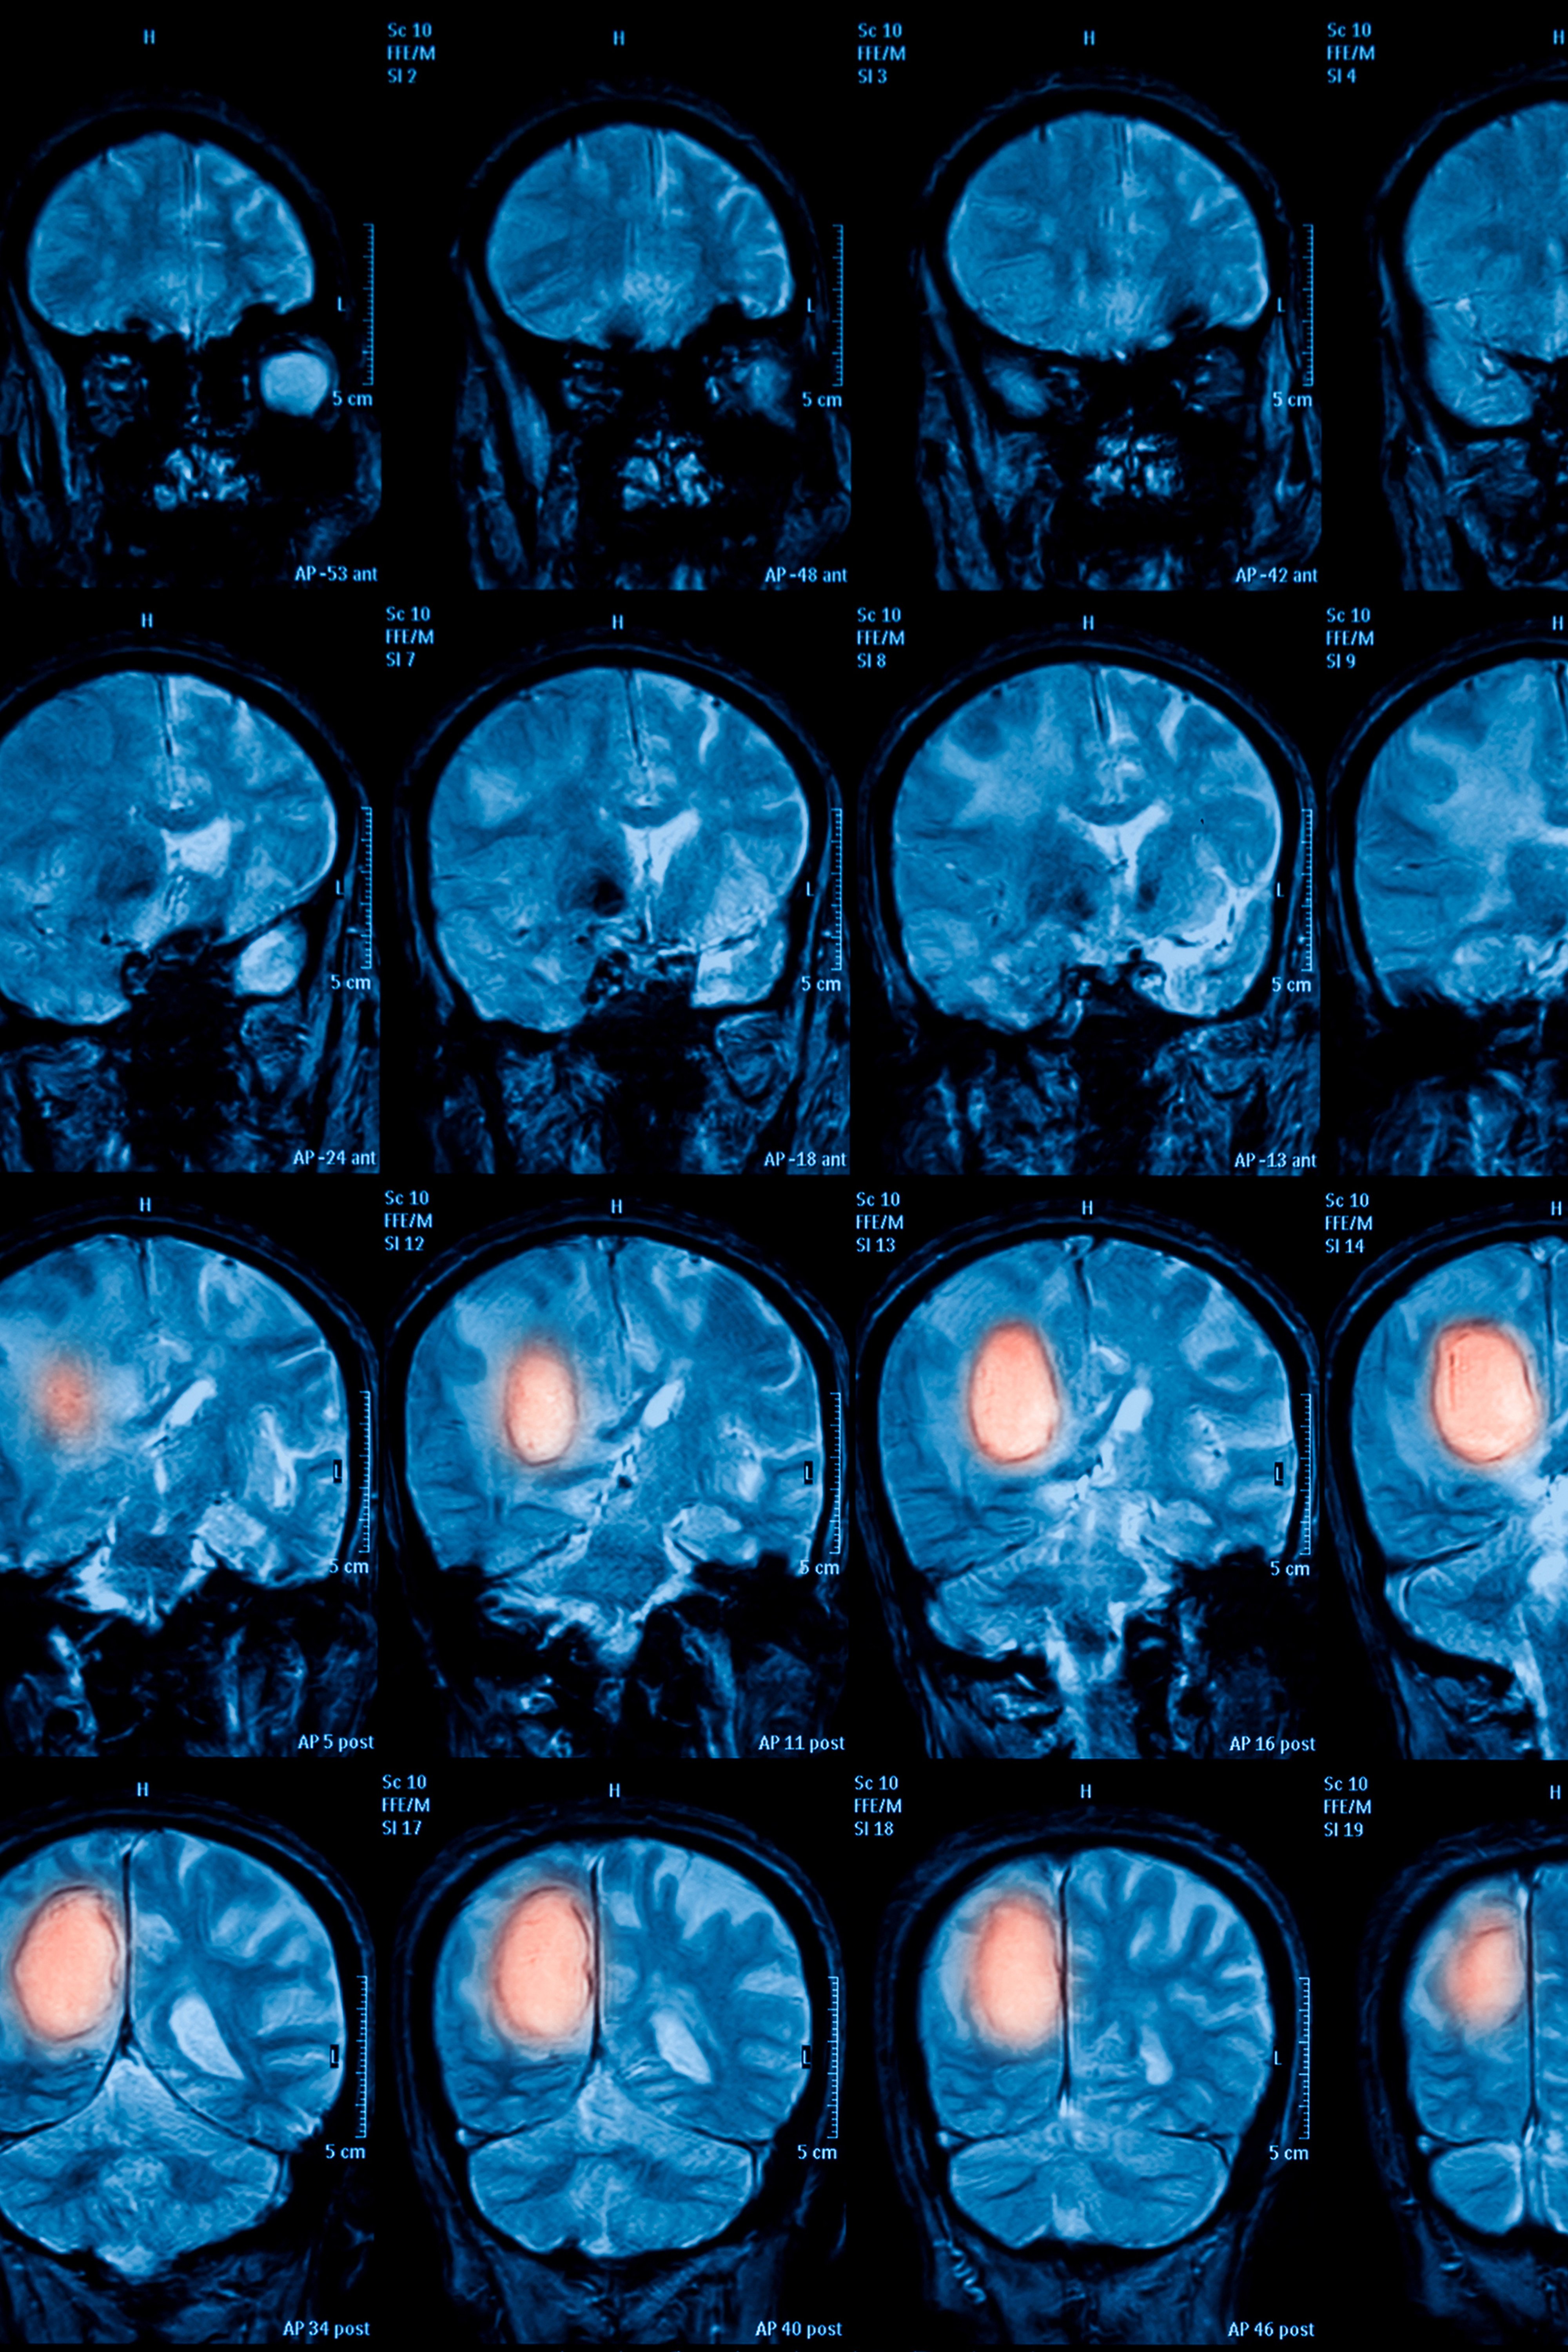

(Wien, 31-01-2019) Neue, zielgerichtete Therapien, die Genmutationen oder spezifische Rezeptoren angreifen, machen bei der Behandlung von Tumoren auch eine immer bessere, molekulare Tumorcharakterisierung notwendig. Die Biologie der Tumorzelle verändert sich durch Mutationen ständig, daher ist eine nicht-invasive diagnostische Methode, die diese Veränderungen exakt abbilden kann von eminenter Bedeutung. Genau das ist das Ziel des heute, Donnerstag, an der MedUni Wien eröffneten „Christian Doppler Labors for Applied Metabolomics“ unter der Leitung des Nuklearmediziners Alexander Haug und des Pathologen Lukas Kenner. Mit Hilfe der Positronen-Emissions-Tomographie (PET) in Kombination mit feingeweblicher Tumoranalyse soll für relevante genetische Veränderungen des Tumors der jeweilige metabolische „Fingerabdruck“ identifiziert werden. Die gewonnenen Muster sollen als Tumor-„Landkarten“ dazu beitragen, den PatientInnen im Sinn der Präzisionsmedizin eine maßgeschneiderte, personalisierte Therapie zu ermöglichen.

„Die Positronen-Emissions-Tomographie ist zwar in der Onkologie weit etabliert, doch nur ein Bruchteil ihres riesigen Potenzials wird im Moment genutzt – und schon gar nicht in Kombination mit der Pathologie. Das ist einmalig“, erklären Haug und Kenner. „In unserem neuen CD-Labor für Applied Metabolomics wollen wir die PET-Bildgebung, histopathologische Untersuchungen, Analysen von Therapie- und prognoserelevanten genetischen Mutationen sowie klinische Daten wie Überleben und Therapieansprechen miteinander verknüpfen. Unser Ziel ist eine nicht-invasive, ‚in-vivo-Pathologie‘, die schließlich zu einem individualisierten Therapiealgorithmus führt.

Um dieses Ziel zu erreichen, wird ein künstliches Intelligenz-Tool für „überwachtes Lernen“, der „Supervised Machine Learning“-Algorithmus angewendet, um aus der Analyse der verfügbaren PET-Daten einerseits die jeweiligen Tumorcharakteristika und andererseits das jeweilige Therapieansprechen zu identifizieren – und diese Daten werden dann mit dem pathologischen Befund abgeglichen. Im 7-Jahreszeitraum des CD-Labors soll es künftig quasi möglich sein, dass man mit einem Blick auf diese Tumor-„Landkarten“ erkennen kann, 1) ob der Tumor bösartig ist; 2) wenn ja, um welchen Tumor handelt es sich – und 3) wie kann dieser Tumor im Sinn der Präzisionsmedizin individuell am besten behandelt werden.

„Das ist der Vorteil, wenn man beide Disziplinen kombiniert: Die Pathologie kann unter dem Mikroskop jede noch so kleine Protein-Aktivität erkennen, im PET sehen wir dann das große Ganze. Je besser wir den Tumor und dessen Mutationen kennen und verstehen, desto besser können wir therapieren. Diese neuartige Methode wird im PET spezifische Muster erkennbar machen, die wir dann in einer Tumor-Kartei katalogisieren können“, erklären die MedUni Wien-Forscher. Später wird man dann wie in einer „Verbrecherkartei“ nach ähnlichen Tumor-Mustern suchen und dementsprechend handeln können. Die Ergebnisse aus dem retrospektiven Teil des Projekts werden mit Hilfe von präklinischen Mausmodellen überprüft.

Untersucht werden im ersten Schritt folgende Tumorentitäten: Karzinome des Darms, diffus großzellige B-Zell-Lymphome sowie Prostatakarzinome. Im weiteren Verlauf soll die Studie auf Brustkrebs und nicht kleinzellige Bronchialkarzinome ausgedehnt werden.